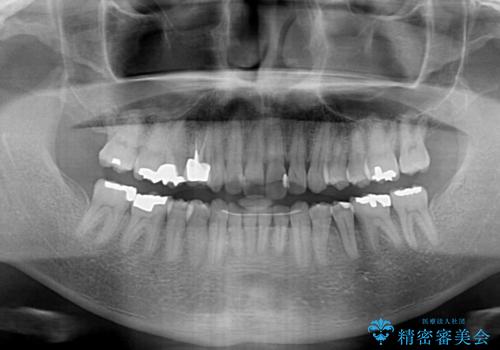

- 外に飛び出した側方の歯と、前歯のデコボコを気にして来院された患者様です。

IPR(歯と歯の間を削る)によってデコボコが解消するように設計し、インビザラインにより治療を行うこととしました。

治療途中で1年半以上通院されない時期があったため、後戻りが生じたことで治療期間が長くなってしまいました。

親知らずを抜去したことで、下顎のデコボコがきれいに解消されました。